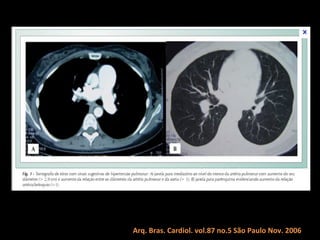

Tomografia computadorizada

Angiotomografia dos vasos pulmonares com TCMD

e reconstruções com filtro de alta resolução;

Mede-se o tronco da pulmonar próximo à sua

bifurcação e lateralmente à aorta ascendente;

Em adultos: até 29 mm;

Sensibilidade: 69-87%;

Especificidade: 89-100%.

Um diâmetro da artéria pulmonar > aorta

ascendente: sensibilidade de 70% e especificidade

de 92% no diagnóstico de HAP;

Arq. Bras. Cardiol. vol.87 no.5 São Paulo Nov. 2006